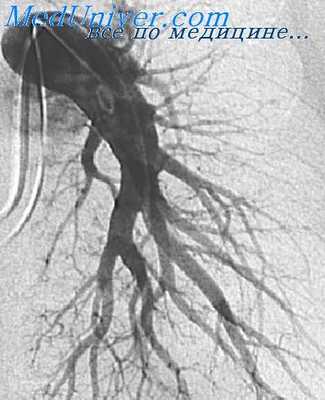

Рис. 3. Концевая ангиопульмонография. Катетер (виден под ключицей, вдоль позвоночника и в области сердца) введен в верхнесегментарную артерию верхней зоны правого легкого. Видны концевые артериальные разветвления. Контрастированы пути венозного оттока данного сегмента

Селективная ангиопульмонография позволяет одновременно измерять давление в полостях сердца и легочного ствола и определять степень насыщения крови кислородом. При концевой пнгиопульмонографии катетер вводят в одну из сегментарных ветвей легочной артерии (рис. 3),после чего инъецируют 5—8 мл контрастного вещества. Кроме описанных методик, ангиопульмонография может быть выполнена путем чрескожной пункции бедренной или подключичной вены по способу Сельдингера (с последующим введением зонда).

Для оценки функции легкого, его отдельных долей и сегментов предложена методика концевой, или терминальной ангиопульмонографии (Semisch, 1959; М. З. Упитер, 1962; Э. С. Шафер, 1964, и др.). Она заключается в медленном, плавном введении через зонд, заклиненный в субсегментарной артерии, 5—10 мл контрастного раствора. На 2—3-й секунде от начала введения при ощущении сопротивления производится одиночный снимок, на котором регистрируются артериальная венозная и капиллярная фазы легочного кровотока.

При данной методике следует вводить контрастный раствор весьма осторожно, чтобы не вызвать разрыва капилляров с выходом контрастного вещества в альвеолы.

Концевая ангиопульмонография позволяет определить состояние периферического сосудистого русла. По степени изменения мелких сосудов и капилляров можно судить о характере и глубине нарушения функции легочной ткани (М. 3. Упитер, 1962).